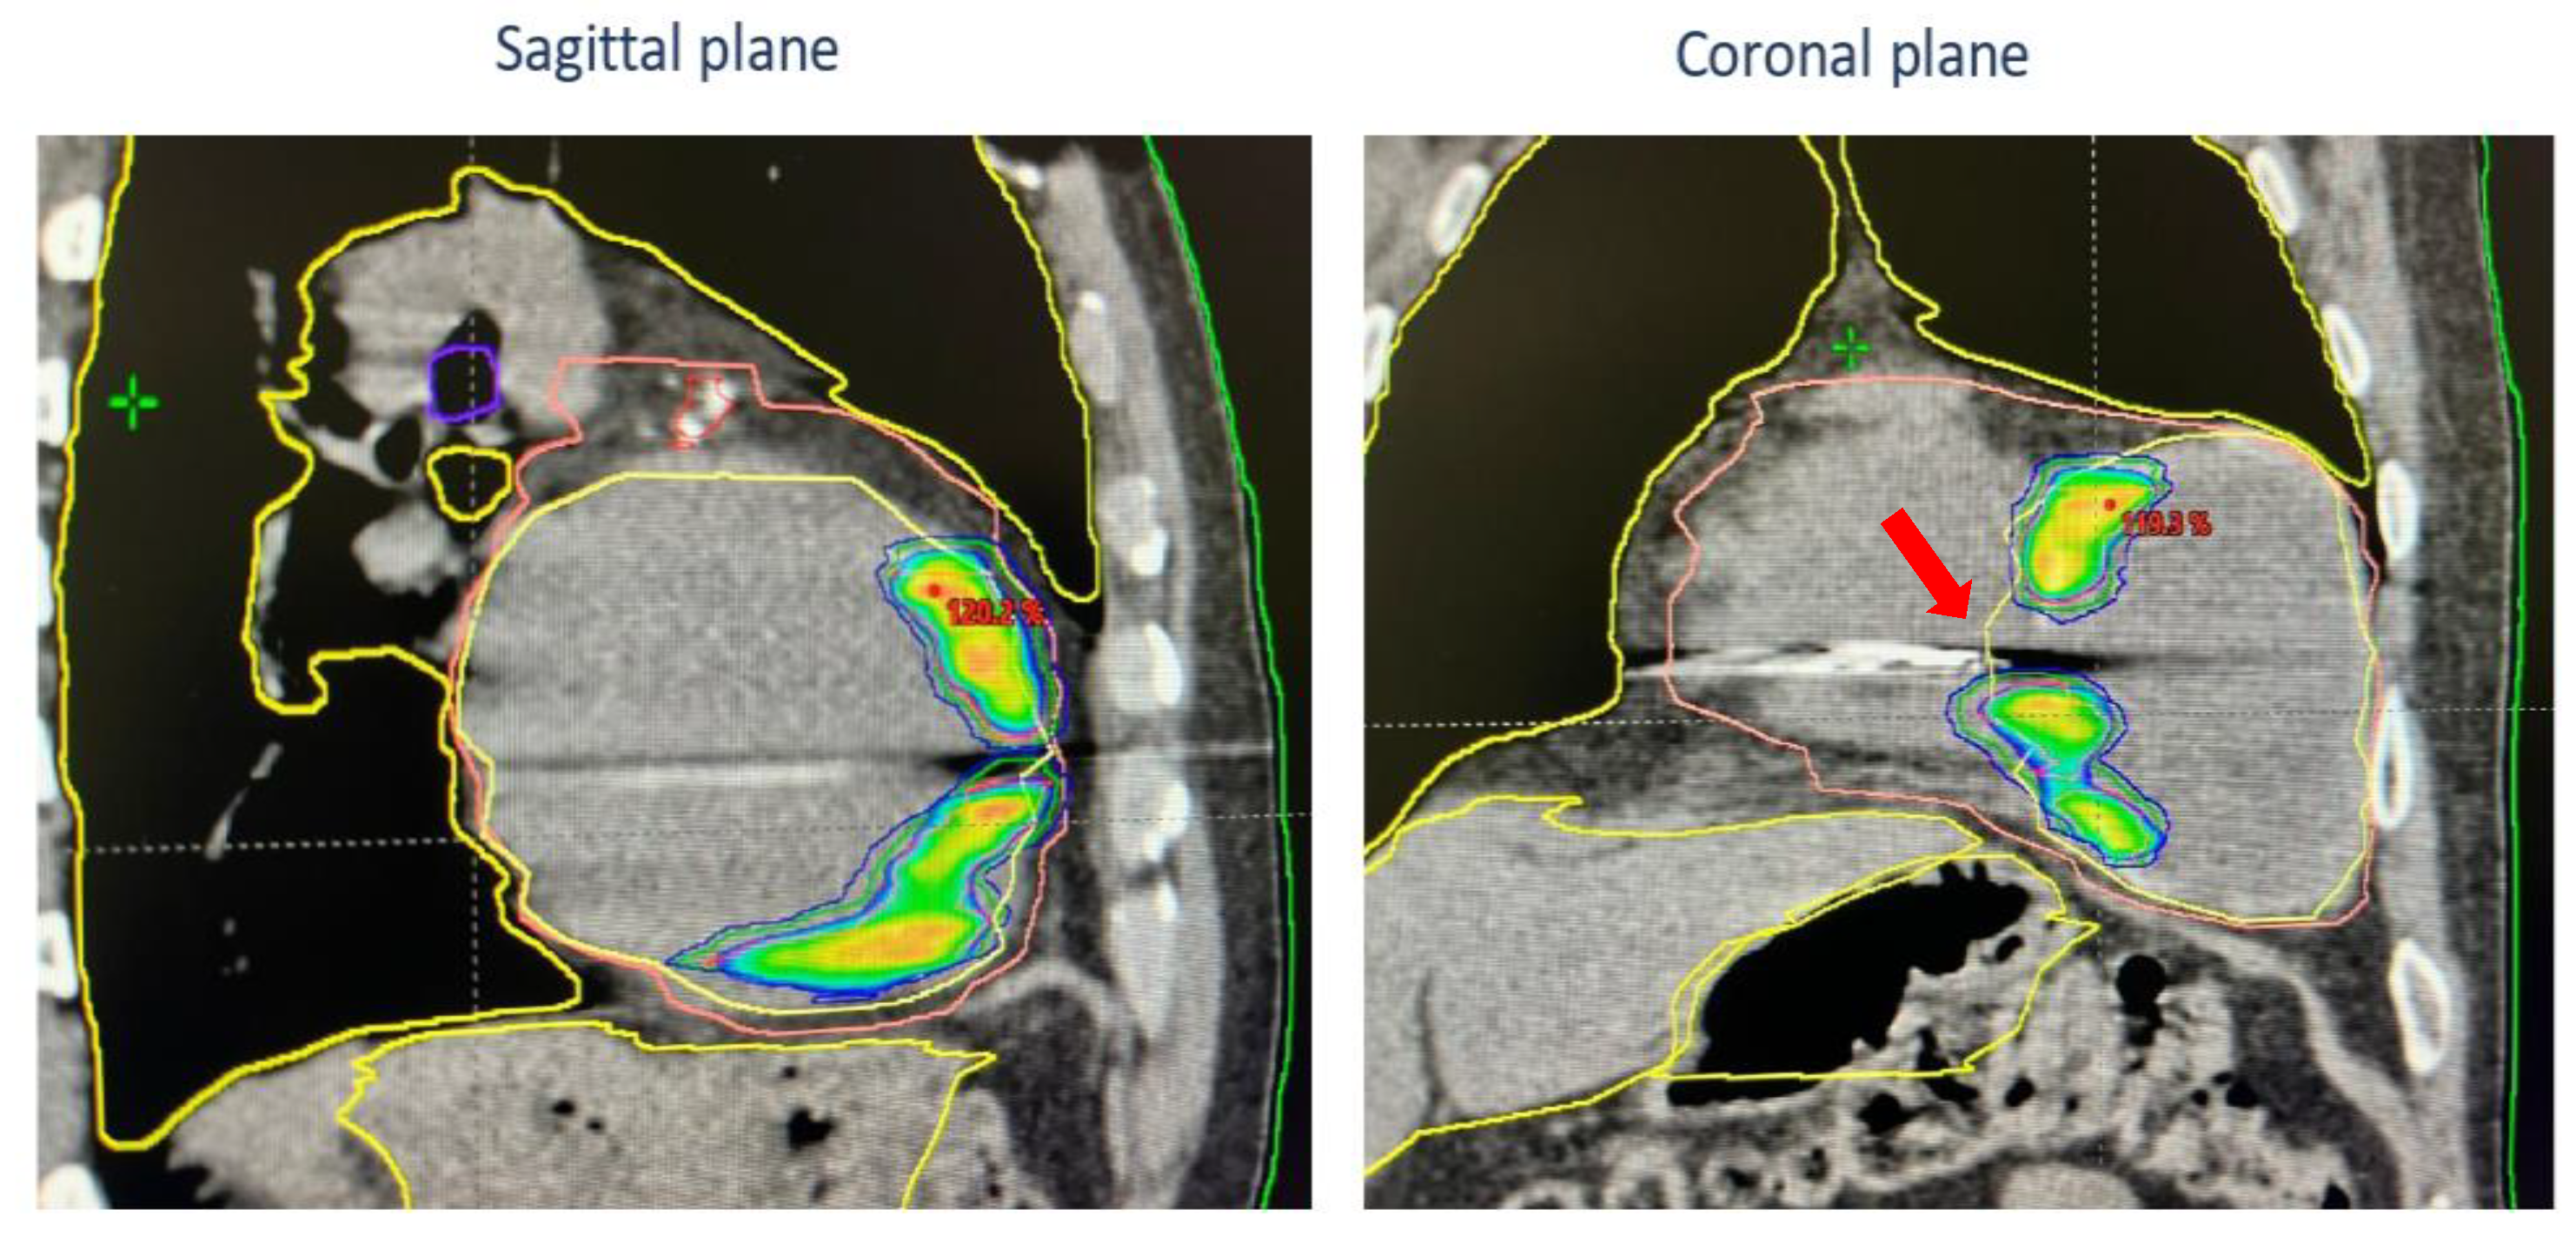

2. Case Presentation